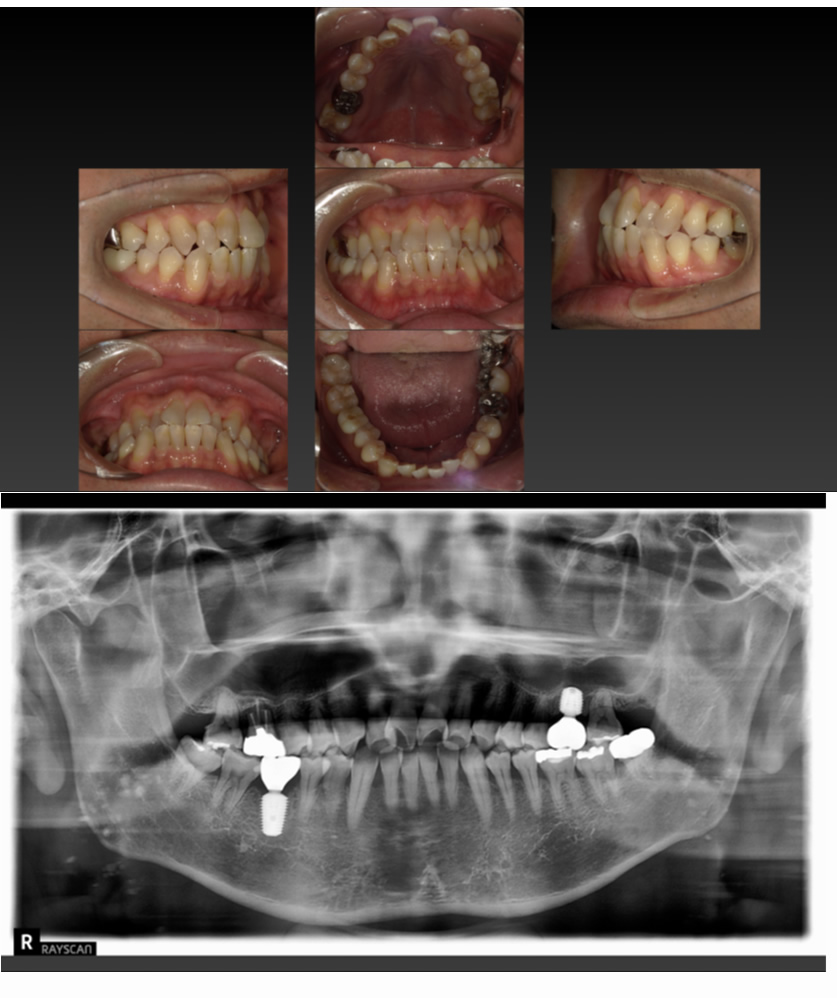

05 症例

歯が割れ、咬むと痛いのでインプラントにしたい

Before

After

| 治療内容 | 歯が割れていて咬むと痛いのでインプラント希望 |

| 患者さま | 60代女性 |

| 主訴 | 咬むと痛いのでインプラントにしたい |

| 治療期間(目安) | 3ヶ月 |

| 治療費(税込:目安) | ¥518,100 |

| リスク | 術後に多少の痛みや腫れが出ることがある。歯肉退縮がおきると、歯と歯肉の間に隙間が生じることがあります。 |